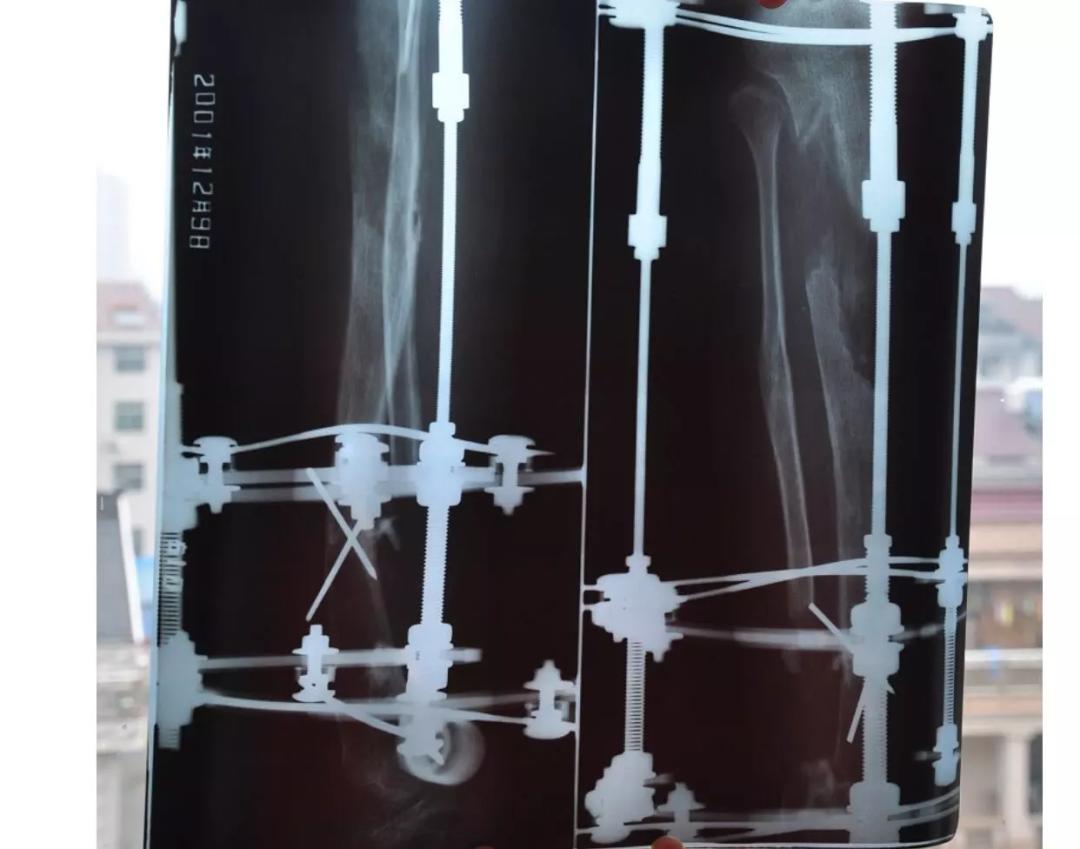

断骨延长手术的原理并不复杂,通俗来讲就是在小腿胫骨上选择一个合适的地方,用钻头打孔,再用锤子把骨头敲断,然后将一套牵引器材套在腿上,为腿部构建一个“稳固的牢笼”,为了保持骨头稳定,医生还会把一些钢针钉在骨头上,之后的几个月,通过调整、牵拉,将断骨的距离每天拉开0.5-1mm,这个速度是由自己控制的,一般负责的医生都会告诉你每天“延长”的长度不能超过1mm,速度太快骨膜会裂掉。

话是这么说,总还是有人心存侥幸、急功近利,想要长得快一点、再快一点,也有一些人刚开始老实,后来发现没什么事就将医生的话抛之脑后了,这种人后来片子拍出来会有10cm左右空在那里,这基本就是终身残疾了,有些人气不过会去找媒体曝光无良医生,殊不知有些恶果其实自己也有责任。